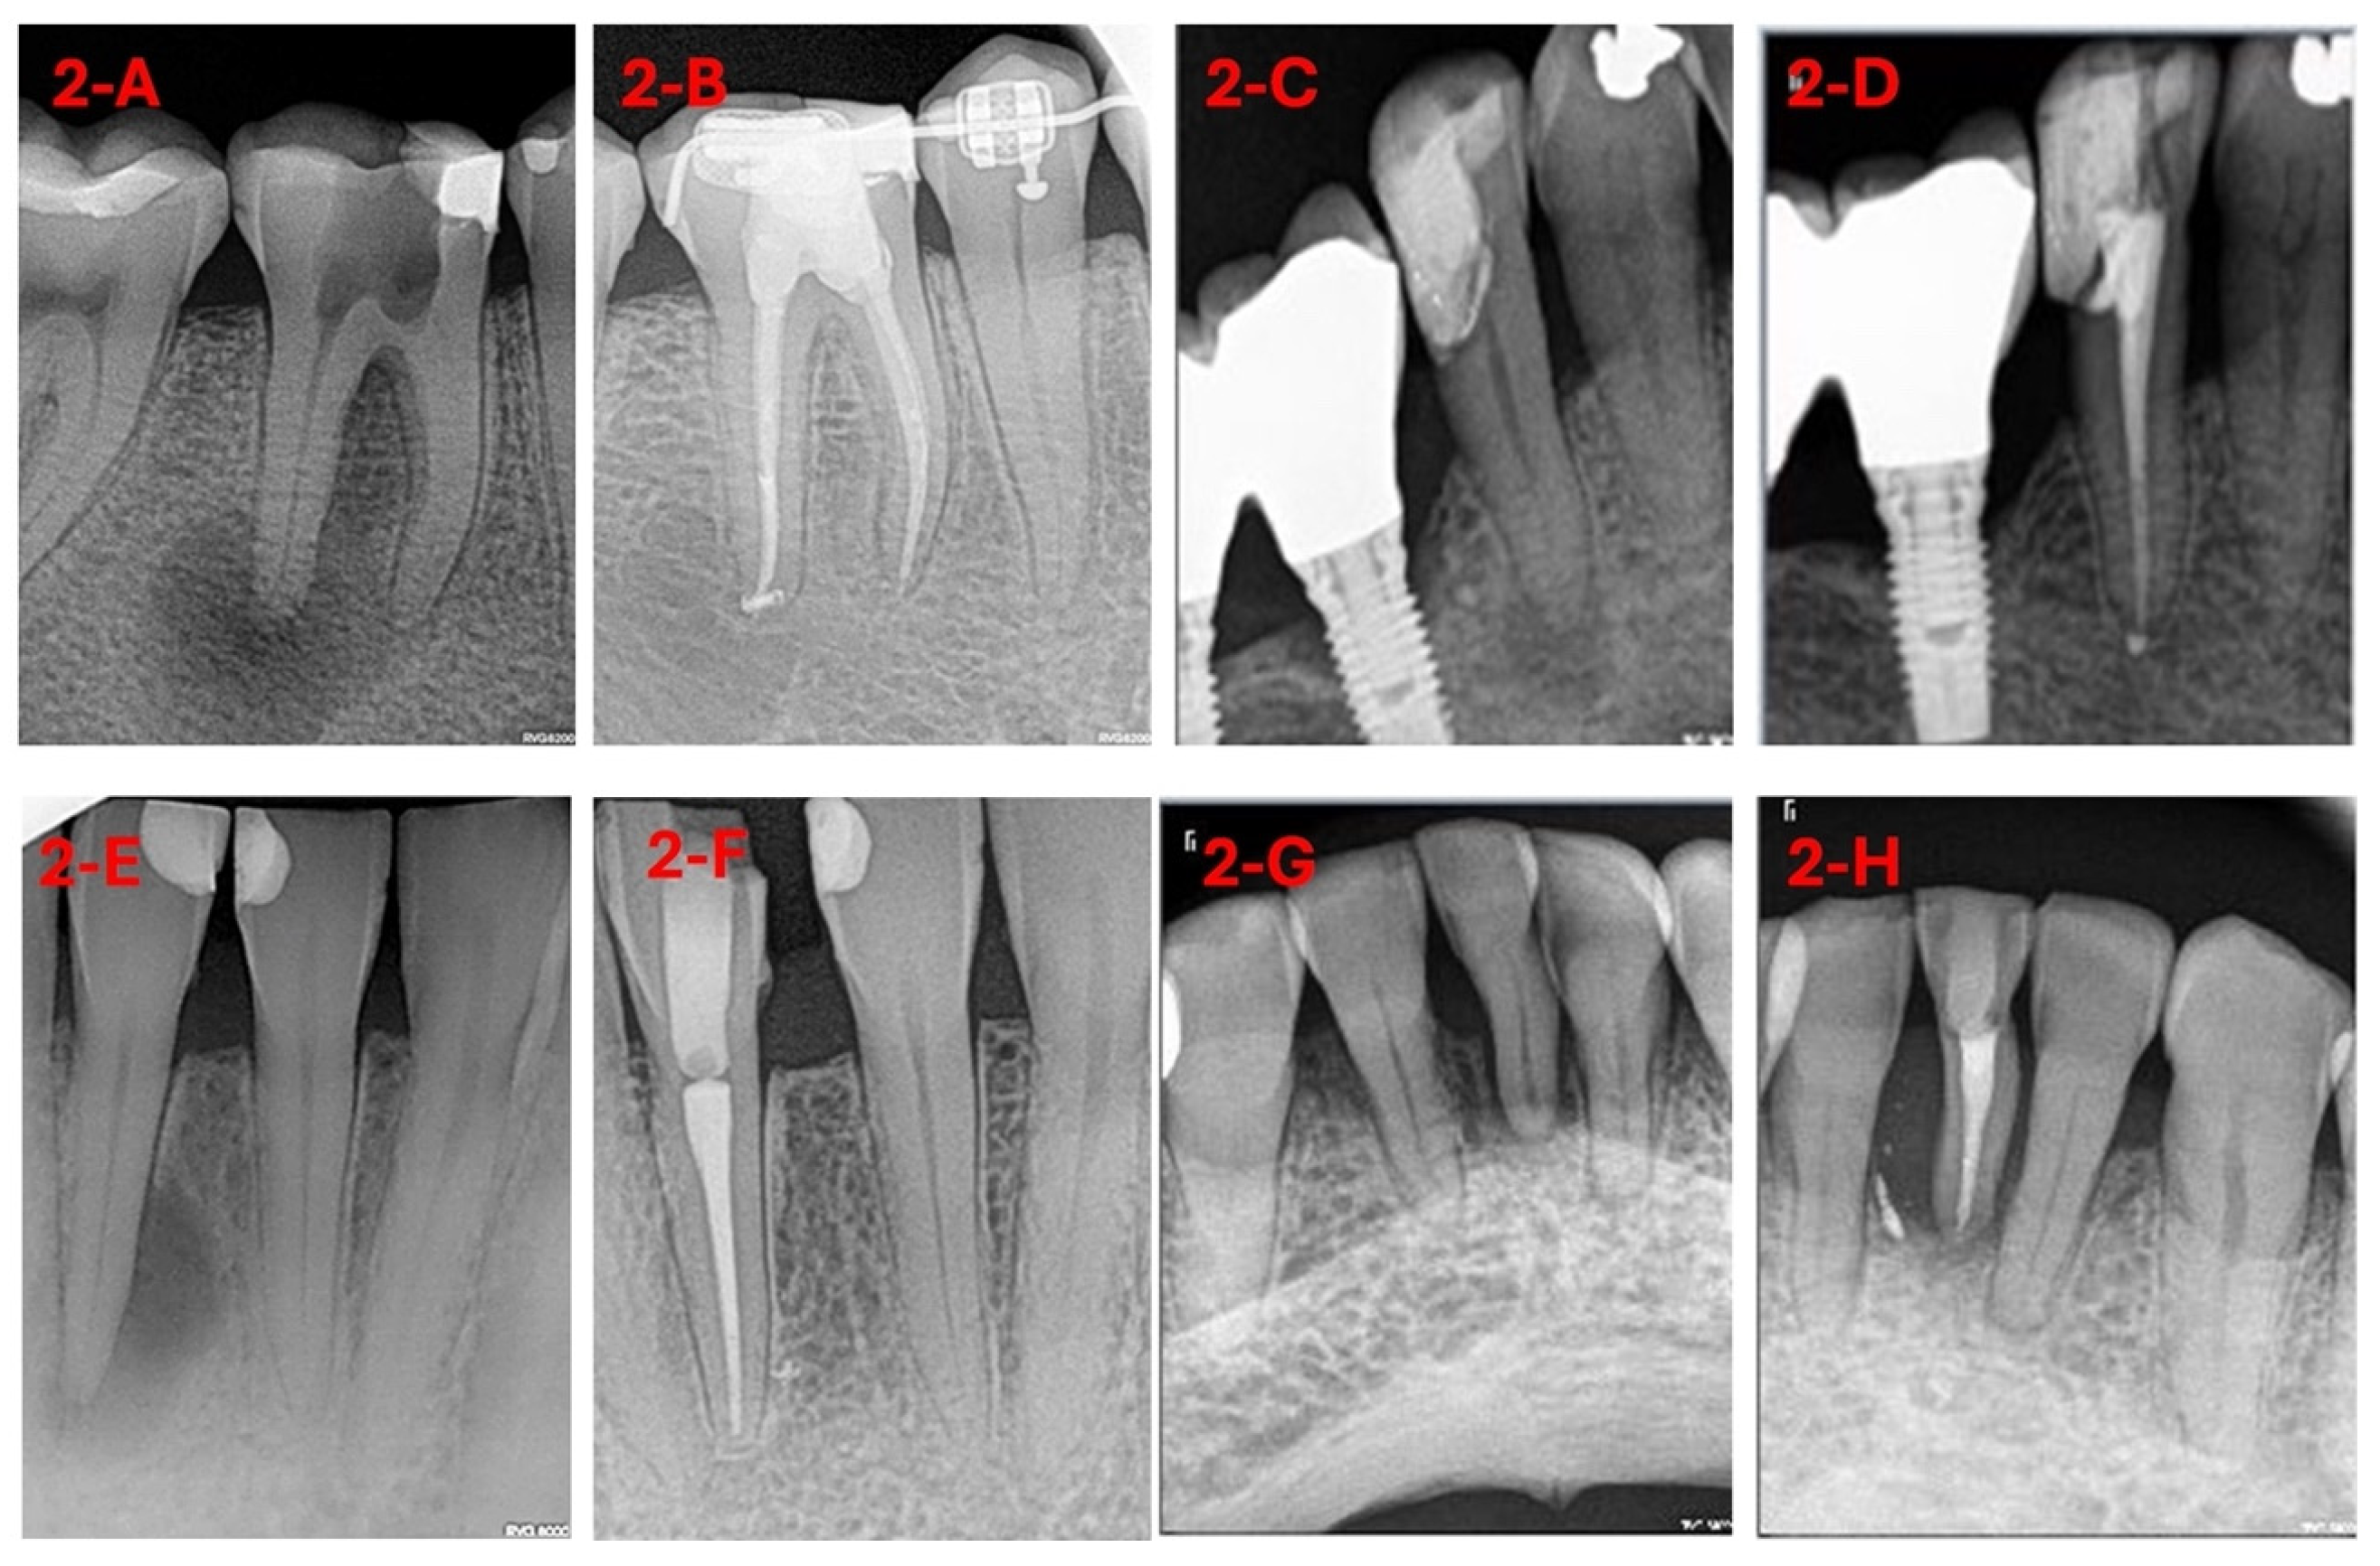

3.1. Sample Selection

3.2. Intervention Procedure

3.3. Machine Learning and Deep Learning Analysis